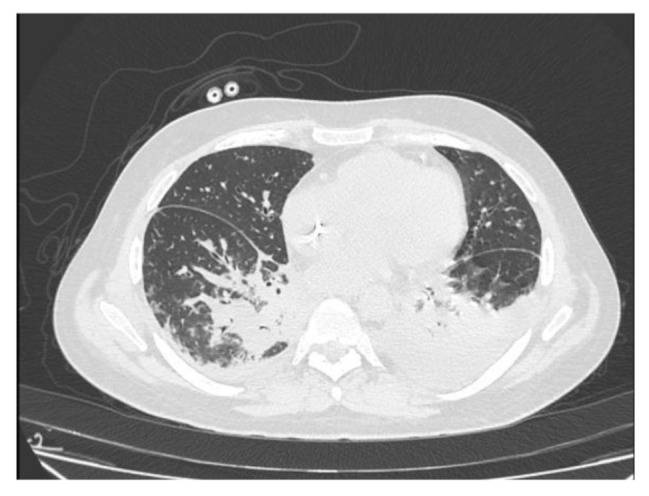

Case presentation: We describe a case of C. indologenes hospital-acquired pneumonia in a 43-year-old HIV-positive patient with multiple comorbidities, including Kaposi sarcoma, diabetes mellitus, and chronic kidney disease requiring hemodialysis. The patient was initially admitted with fever and elevated inflammatory markers, and empirical broad-spectrum antibiotic therapy was initiated. Despite initial improvement, the patient developed respiratory failure, requiring oxygen therapy. A respiratory panel identified Rhinovirus, while sputum culture revealed C. indologenes, resistant to multiple antibiotics but susceptible to levofloxacin. Targeted therapy led to clinical improvement. However, the course was complicated by Clostridioides difficile-associated diarrhea, followed by fatal sepsis due to Klebsiella pneumoniae. Our review of the literature identified 71 reported cases, with bacteremia (51%) and pneumonia (29%) as the most common clinical presentations. Medical devices and prolonged antibiotic exposure were key risk factors. While C. indologenes is intrinsically resistant to beta-lactams and carbapenems, fluoroquinolones and trimethoprim-sulfamethoxazole demonstrated efficacy in most cases. Emerging therapies, such as cefiderocol, may provide additional options for multidrug-resistant strains. This case highlights the critical need for accurate microbial identification, targeted therapy, and vigilant antimicrobial stewardship to improve outcomes in vulnerable patient populations.